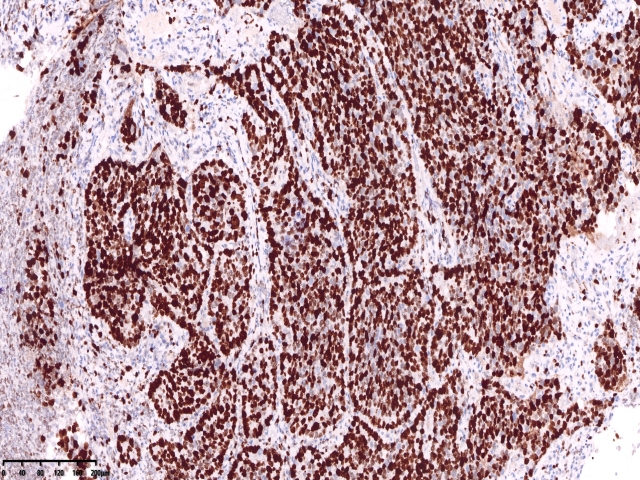

KI67